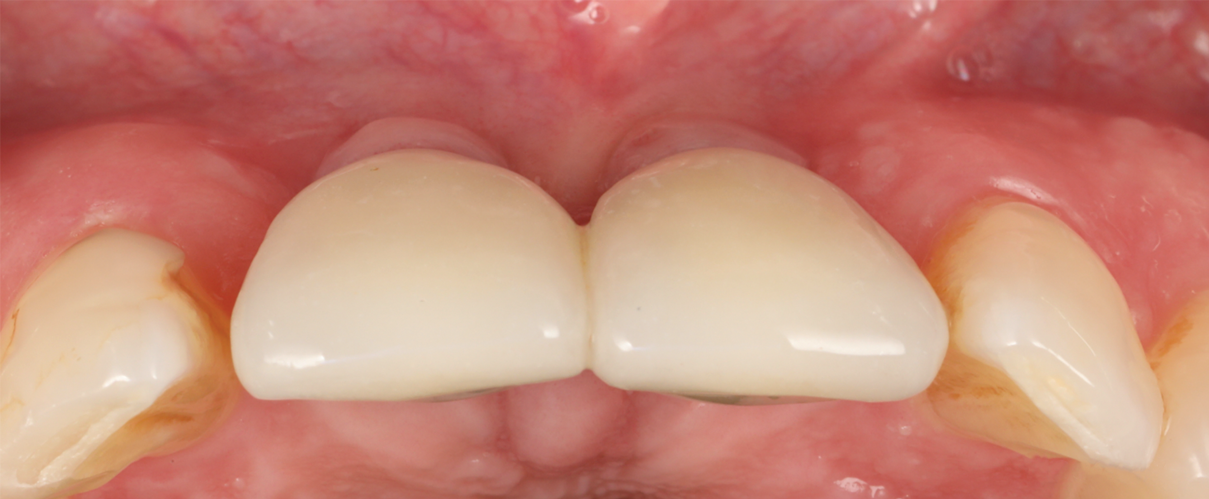

A 46-year-old systemically and periodontally healthy woman presented to the Graduate Periodontics Clinic at the University of Michigan School of Dentistry with the chief complaint of poor esthetics of her smile due to two dental implants (Nos. 8 and 9) showing their metal components (Figure 1). The patient reported that the implants had been placed 15 to 20 years previously after an accident. Clinical examination revealed that the implants had probing depths within 3 mm (facial probing depth of 3-2-3 mm for implant No. 8 and 2-2-2 mm for implant No. 9), no bleeding on probing, and no suppuration; the implants were therefore diagnosed as healthy (Figure 1 and Figure 2). The papilla between the two implants was deficient on the buccal aspect. The implants were buccally positioned, and a substantial lack of soft-tissue volume was noted.

Fig 1. Clinical view at presentation.

Figure 1

Fig 14. Final outcome at 1 year.

Figure 14

Fig 15. Clinical comparison of the volumetric gain obtained with the intervention, frontal views. Fig 15: Frontal view at baseline. Fig 16: Frontal view at 1-year post-treatment.

Figure 15

Fig 16. Clinical comparison of the volumetric gain obtained with the intervention, frontal views. Fig 15: Frontal view at baseline. Fig 16: Frontal view at 1-year post-treatment.

Figure 16